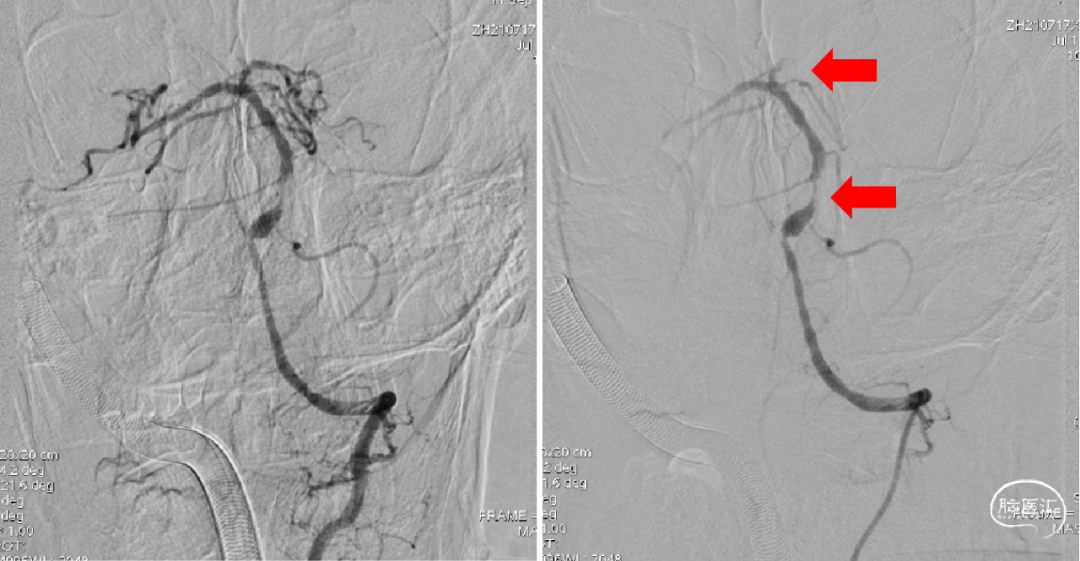

1、选择右侧椎动脉入路;2、造影提示V4段近端狭窄,远端未见显影。

右侧颈动脉造影未见明显后交通开放,可见基底动脉末端显影(红色箭头)。